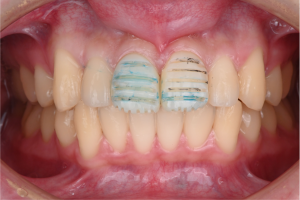

※上顎両側中切歯にプロビジョナルレストレーション(仮歯)を装着した際の口腔内写真

矯正治療がある程度進み、歯並びが整ってきた段階で、形にバランスの乱れがある上の前歯2本に、貼り付けるタイプの仮歯を装着しました。

この時点では、歯を削る処置は行っていません。

※上顎両側中切歯に仮歯を装着した状態

この症例では、歯科技工士が作製した仮歯をいったん装着し、見た目やバランスを確認しました。